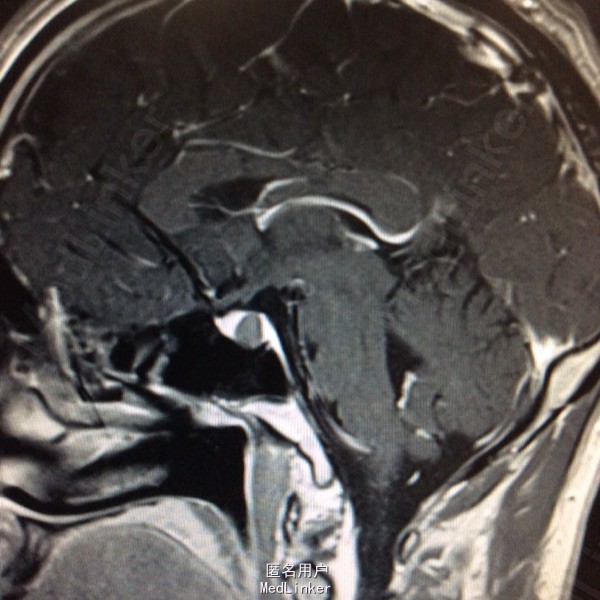

查体未见明显阳性体征,发育正常 头颅CT提示鞍区少量出血 MRI增强提示鞍区占位病变,大小约0.8*1.5cm 考虑垂体瘤卒中

术前诊断:垂体瘤 择期行经蝶入路垂体瘤切除术 术后病理提示垂体腺瘤